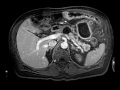

Chronic pancreatitis

Multiple MRI images demonstrate diffuse T1 hypointensity of the pancreas with a dilated pancreatic duct and at least 2 discrete cystic lesions in communication with the pancreatic duct, representing chronic pancreatitis with pseudocysts